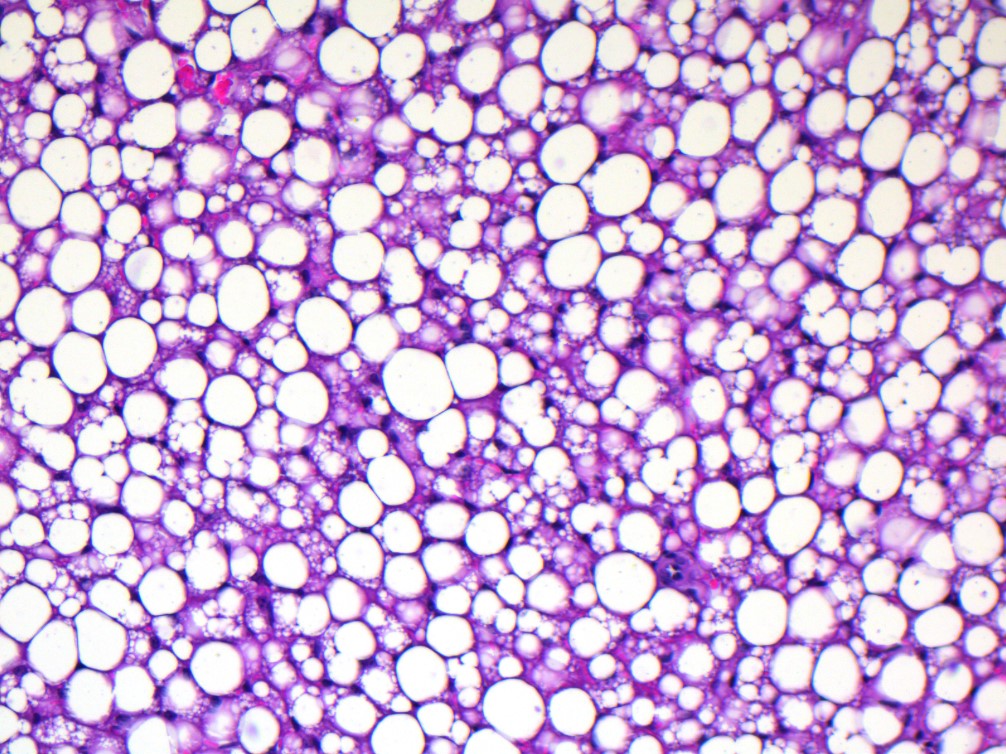

STAT5 Transkriptionsfaktoren im braunen Fett: „Schalter“ gegen Übergewicht?